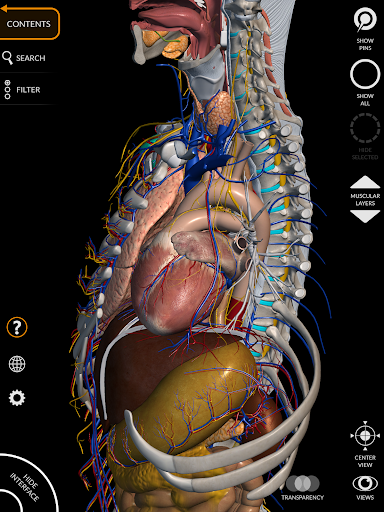

"Anatomy 3D Atlas" cho phép bạn nghiên cứu giải phẫu người theo cách dễ dàng và tương tác.

Thông qua giao diện đơn giản và trực quan, bạn có thể quan sát mọi cấu trúc giải phẫu từ mọi góc độ.

Các mô hình giải phẫu 3D đặc biệt chi tiết và có kết cấu lên đến độ phân giải 4k.

Việc phân chia theo vùng và chế độ xem được xác định trước giúp quan sát và nghiên cứu các bộ phận hoặc nhóm hệ thống riêng lẻ và mối quan hệ giữa các cơ quan khác nhau.

• Hệ thống cơ xương

• Hệ thống tim mạch

• Hệ thống thần kinh

• Hệ thống tiêu hóa • Hệ thống tiết niệu sinh

• Xoay và phóng to từng mô hình trong không gian 3D

• Tùy chọn ẩn hoặc cô lập một hoặc nhiều mô hình đã chọn

• Bộ lọc để ẩn hoặc hiển thị từng hệ thống

• Hình dung các cơ qua các lớp từ lớp nông đến lớp sâu nhất